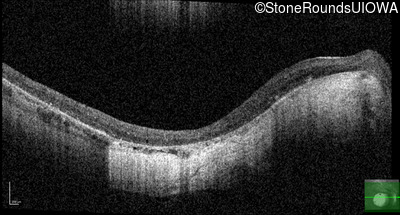

Age at visit: 15 years

OD OS

This 15 year old male had a macular abnormality noted two weeks ago when he was refracted for his first pair of glasses. Bone spicule-like pigmentation was first noticed a year later (age 16) during a routine follow-up eye exam.

Age at visit: 16 years